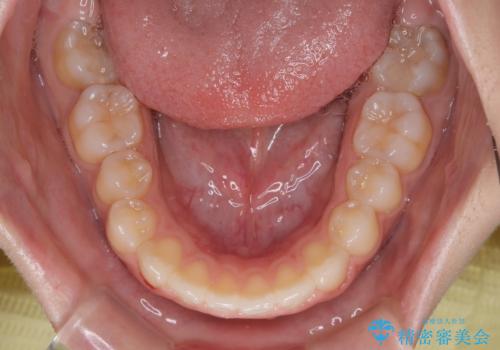

再矯正 開咬に後戻りした歯列をインビザラインで改善

- 矯正治療の後戻りを気にして来院された患者様です。

デコボコと上下前歯の隙間が気になるものの、しっかりと治療をしたいという意思はないとのことで、インビザラインの中でもアライナー数に制約のあるライトパッケージを用いて、治療できる範囲まで歯列を改善していくこととしました。

インビザラインは前歯部の開咬に効果的であることが多く、ライトパッケージにもかかわらず、十分満足のいく仕上がりとなりました。